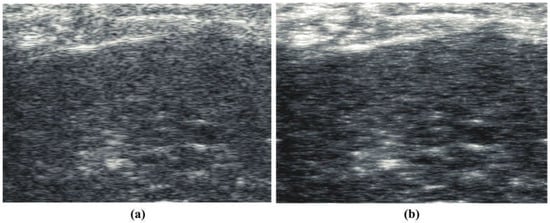

In this section, we examine standard B-scan envelope images and their reconstruction using steps (i)–(iii) in Section 3 and produce an ensemble average of five independent realizations of the random Gaussian noise scatterers used in the initial steps. First, a normal rat liver on a standard diet is shown in Figure 1a from a study approved by the Institutional Animal Care and Use Committee (IACUC) at the University of Texas at Dallas []. The rat liver scan data were obtained using a Vevo 3100 scanner (FUJIFILM VisualSonics Inc., Toronto, ON, Canada) with a 15 MHz center frequency linear probe (MX201) [] and with the beamformed RF sampled at 50 MHz. This image and subsequent B-scan images are displayed in the conventional sense, on a log amplitude scale of approximately 50 dB dynamic range. The power law reconstruction, or “thru-scan”, is shown in Figure 1b. Note the alternative tissue rendering, presenting a different type of texture, arguably representing the anatomical hepatic structure comprising extensive fluid (hypoechoic) channels. Also seen in Figure 1b is the emergence of small hyperechoic spots, which are usually linked to the local maxima of the original envelope. The possible link of these hyperechoic foci to scattering structures is explored further in Appendix A.

Figure 1.

(a) Conventional B-scan at 15 MHz from a control group rat liver, in vivo. (b) Constrained reconstruction from power law principles, which we call “thru-scan”, demonstrating a modified texture across the liver interior and the emergence of specific hyperechoic points, many of which appear coincident with the local maxima of the original envelope. The images are displayed conventionally using log-compressed 50 dB dynamic range grayscale.